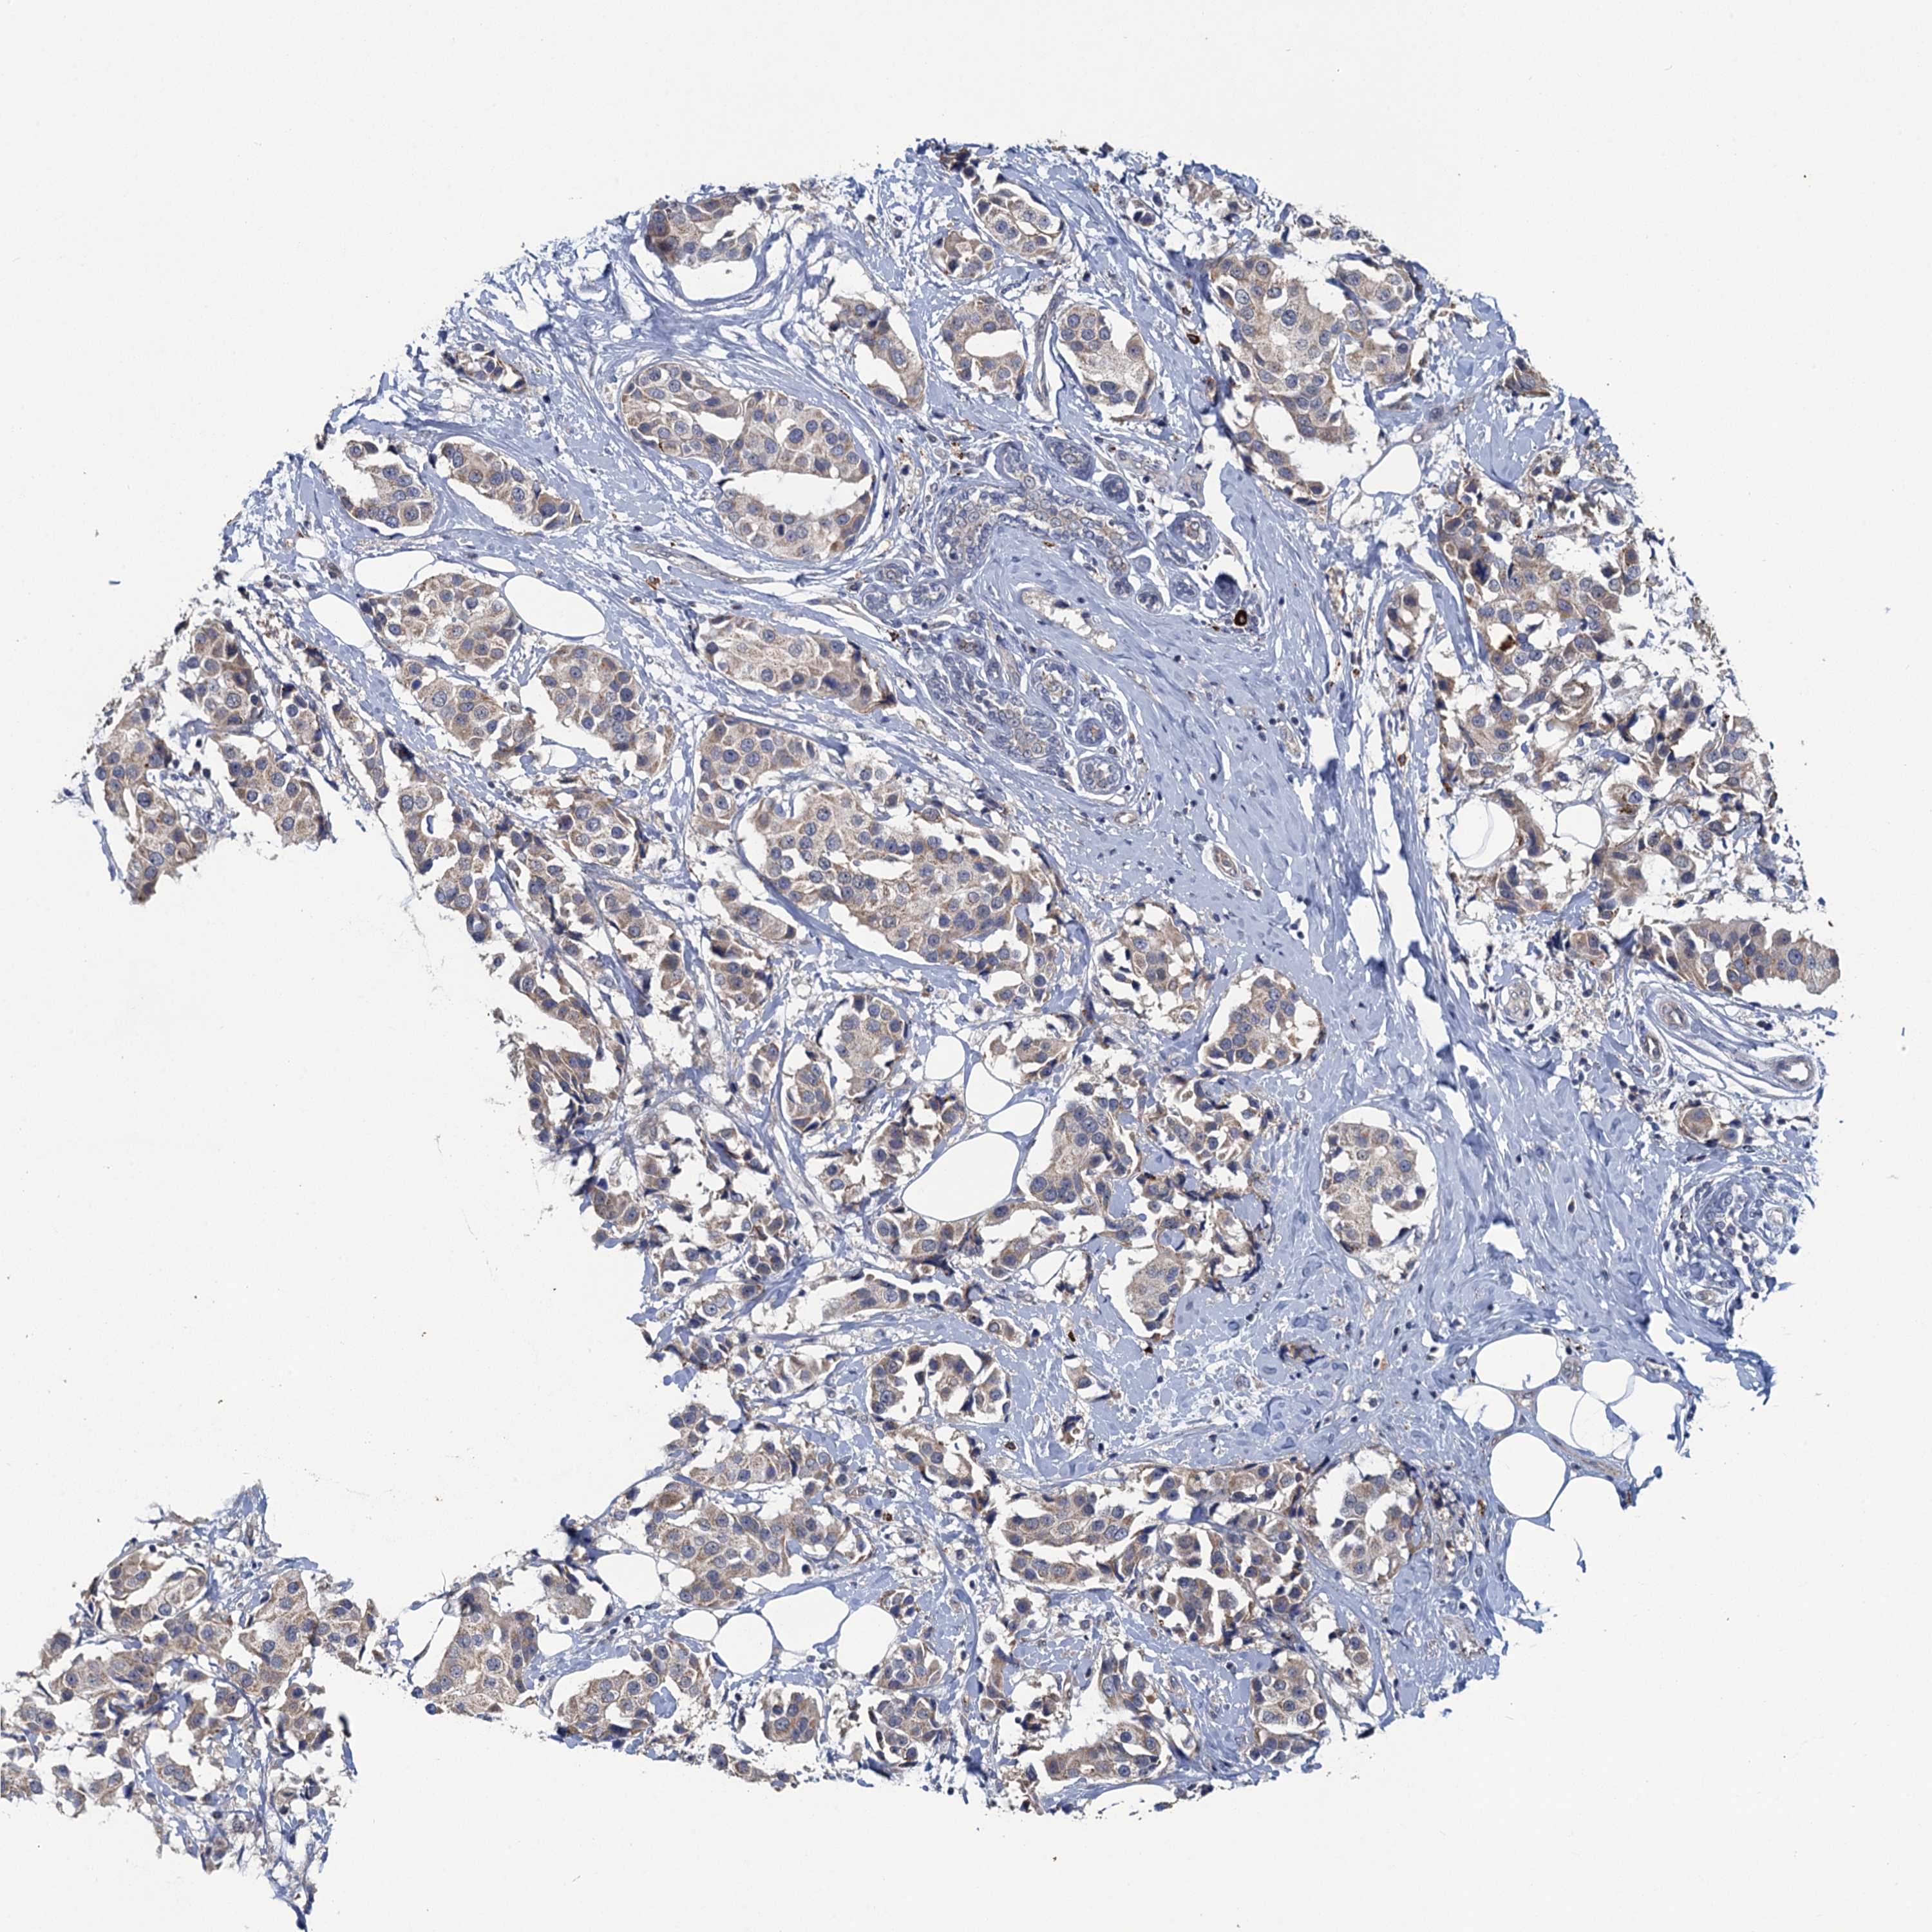

CANCER BREAST CANCER Show tissue menu

BRCA TCGA BRCA VALIDATION PROTEIN EXPRESSION